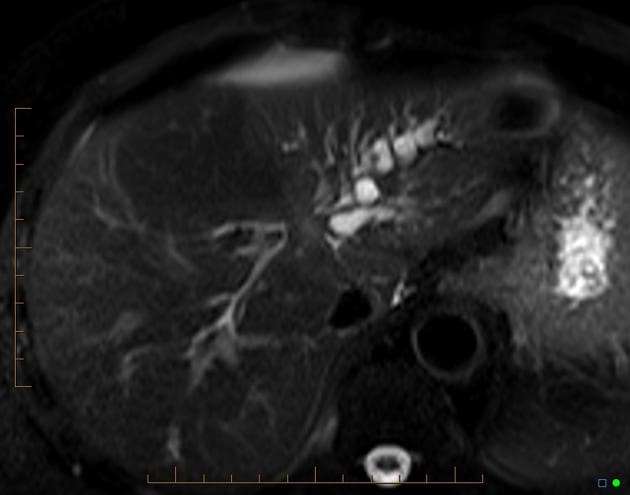

- MRCP (cắt ngang theo mặt phẳng vành): các ống mật gan trong (IHBD) giãn, có đoạn hẹp tại ống mật chủ (CBD) đoạn gần. Ống tụy không có bất thường.

- "MRCP là phương tiện hình ảnh không xâm lấn quan trọng để đánh giá giải phẫu đường mật và xác định vị trí tắc mật."

Ung thư ống mật tế bào gan vùng cửa gan, còn gọi là u Klatskin, là khối u ác tính xuất phát từ biểu mô của các ống mật gần, đặc biệt tại vị trí nối ống mật gan phải và trái. Bệnh thường khởi phát âm thầm với các triệu chứng không đặc hiệu như vàng da, ngứa, sụt cân, gây khó khăn trong chẩn đoán. Trên hình ảnh, tổn thương điển hình là khối u vùng cửa gan gây giãn ống mật theo phân thùy, với dấu hiệu 'cắt cụt' trên chụp đường mật. MRCP rất nhạy trong việc xác định mức độ và phạm vi tắc mật. Trên MRI có tiêm thuốc, khối u thường giảm tín hiệu và tăng quang kém trên các dãy T1 và T2. Việc phân biệt với các đoạn hẹp lành tính, đặc biệt trong viêm đường mật xơ hóa tiên phát, có thể khó khăn và cần sinh thiết hoặc đánh giá nội soi. Chẩn đoán sớm rất quan trọng để xem xét cắt bỏ phẫu thuật hoặc ghép gan, mặc dù phần lớn các trường hợp khi chẩn đoán đã không còn khả năng cắt bỏ.